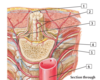

1

1 - posterior spinal arteries

2

2 - anterior spinal arteries

3

3 - anterior radicular artery

4

4 - dorsal branch of posterior intercostal artery

5

5 - posterior intercostal artery

6

6 - thoracic (descending) aorta

7

7 - anterior segmental medullary artery

8

8 - anterior spinal artery

9

9 - pial arterial plexus

10

10 - right posterior spinal artery